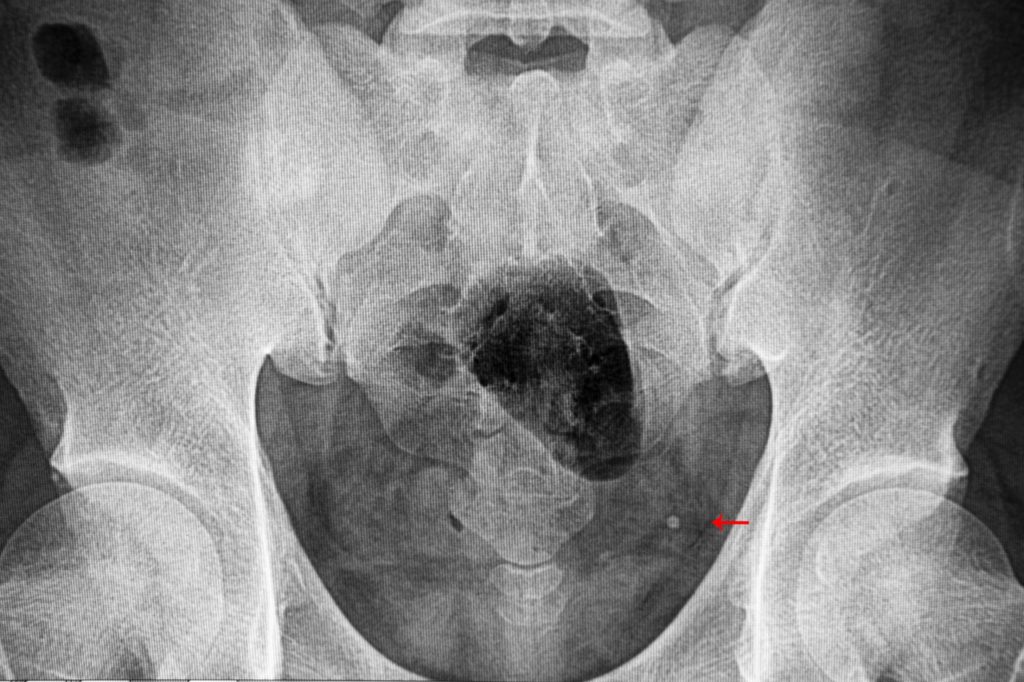

If you’ve been diagnosed with a stone in the urethra, you will need a ureterolithotomy in Las Piñas as treatment. This can be difficult, especially if left untreated. Having stones in your urethra is a symptom called bladder stones. Bladder stones develop when minerals in your urine are concentrated. This concentration becomes crystallized and forms different sized stones within your urethra.

Small-sized stones can go away without treatment but if you’ve been diagnosed with larger stones you will need this surgery or different medications to assist in healing. Here’s what ureterolithotomy is all about.